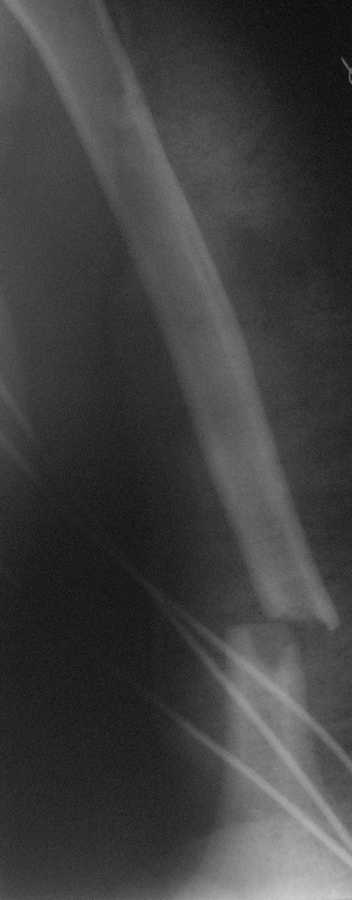

Уважаемый товарисч.Данный перелом можно вылечить антероградным, ретроградным штифтованием, пластиной, аппаратом внешней фиксации, вытяжением за локтевой отросток на шине ЦИТО. Учитывая наличие тяжелой ЧМТ предпочтение должно отдаваться минимальноинвазивной технике.

Качество паредставленных Вами рентгеновских снимков крайне низкое, что косвенно свидетельствует об общей культуре работы в Вашем отделении.